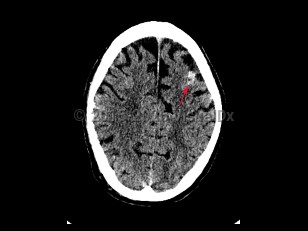

Subarachnoid hemorrhage (SAH) is bleeding directly into the cerebrospinal fluid (CSF) within the subarachnoid space that surrounds the brain. It usually presents as a severe sudden-onset headache, often described as the worst headache of the patient's life, with radiation of pain down the neck and back. Onset of headache may be accompanied by a brief loss of consciousness, nausea, vomiting, and meningismus. SAH occurs in about 10 per 100 000 people per year. Incidence increases with age and peaks in the sixth decade of life. Risk factors include female sex, smoking, alcohol use, drug abuse, hypertension, oral contraceptive use, known cerebral vascular malformation, collagen vascular disease, and family history of SAH. In the United States, African Americans are at higher risk.

Cerebral aneurysms > 5-7 mm are most likely to rupture. Approximately 1%-3% of patients visiting the emergency department for a headache are subsequently found to have a SAH. Trauma is the most common cause of SAH; however, nontraumatic SAH is found to result from a ruptured saccular aneurysm in 80% of cases. Patients with SAH require close monitoring and often require intensive care unit admission.